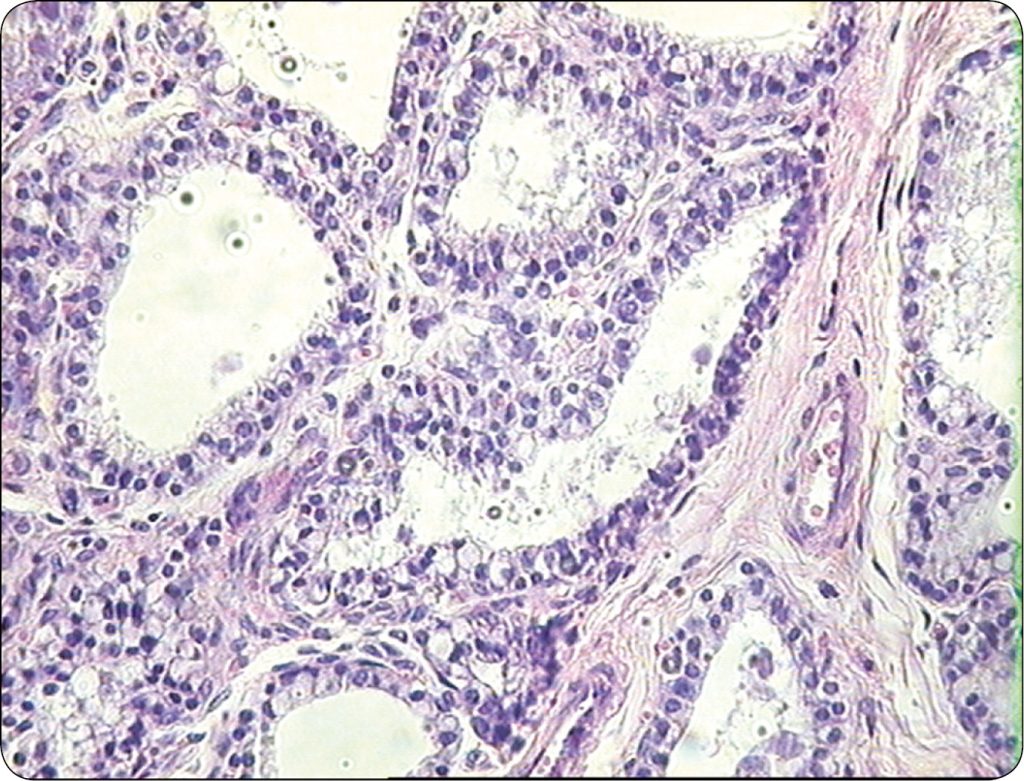

Uszkodzenie tkanki gruczołowej wyrażało się obecnością w strukturze komórkowej gruczołu mlekowego charakterystycznych cech patologicznych, a mianowicie były to: torbiele powstałe z pęcherzyków wydzielniczych, metaplazja apokrynowa komórek nabłonka gruczołowego, włóknienie zrębu gruczołu, proliferacja pęcherzyków, rozrost komórek nabłonka gruczołowego i komórek myoepitalialnych, rozrost gruczołowy (adenosis) z równoczesną proliferacją zrębu łącznotkankowego gruczołu, a także brodawczaki dużych przewodów gruczołowych. Wyrazem zalegania mleka pęcherzykowego jest obecność w świetle pęcherzyków gruczołowych, tzw. ang. milk calcium, czyli inkrustowanej solami wapnia wydzieliny gruczołu. Niektóre z wymienionych typów zmian patologicznych stwierdzonych w gruczole mlekowym krów chorych na adenomyosis/endometriosis ilustrują ryc. 2 i 3. Podobne zmiany patologiczne stwierdzano w gruczole sutkowym suk, u których ponadto występowały różnego typu guzy nowotoworowe (7).

Należy podkreślić, że zmiany patologiczne stwierdzano we wszystkich badanych ćwiartkach gruczołu mlekowego krów chorych na adenomyosis/endometriosis, przy czym były one różnorodne u [...]